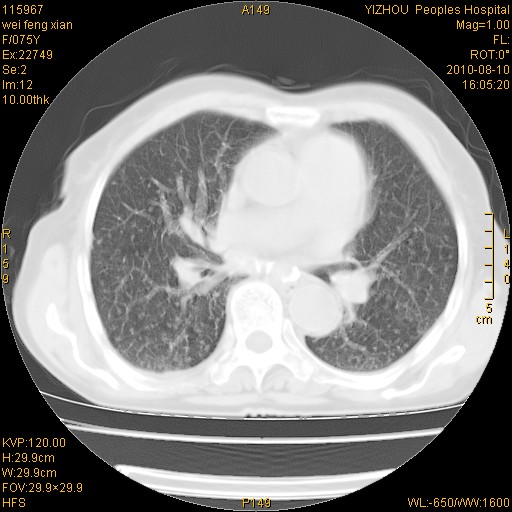

双肺间质增生并右肺上叶炎性改变,不除外右肺上叶结核病肺内播散

考虑慢支伴右上肺慢性感染可能性大,建议结合临床排外尘肺可能。

考虑尘肺可能性大.

考虑右肺上叶炎症合并双肺结核可能性大,建议上传纵隔窗ct图片。

如果患者是男性首先考虑尘肺,但现在即是是女性也要询问职业病史。

双肺结核可能性大

考虑尘肺并结核;右上肺支气管扩张!

结核、尘肺、支气管肺泡癌都不能除外

右肺上叶继发性肺结核伴肺内血型播散!

考虑右肺上叶继发性肺结核伴两肺播散。